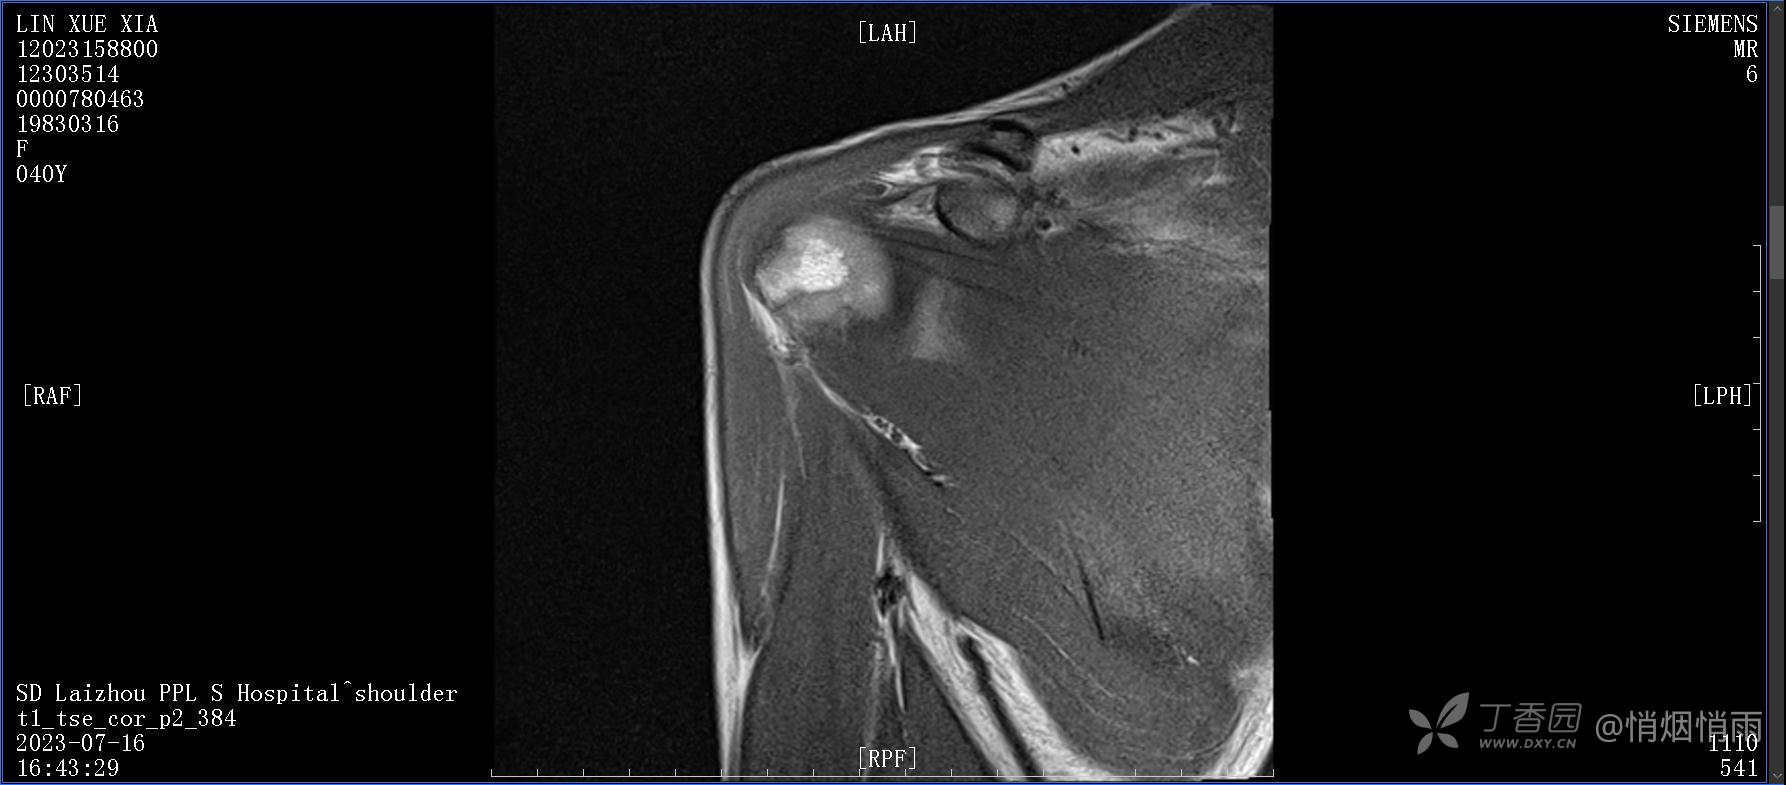

查体:右肩关节局部轻度肿胀,肩胛区压痛明显,痛处不固定,肩关节痛性活动受限,jobe test(+),lift -off test(+),中指、环指感觉较余指减退,余肢端感觉及血运情况可。

目前的诊断,暂时依据辅助检查诊为肩袖损伤,但是患者疼痛的性质和特点,却不是单纯的肩袖损伤所致。考虑过胸廓出口综合征,但是该疾病会出现肩胛区的疼痛吗?(由于考虑到费用的问题,没再进行下一步的检查)带状疱疹会有如此的症状吗?